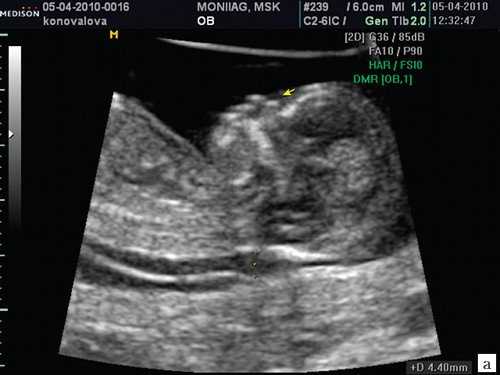

Цель 3D-ультразвукового исследования состоит в создании объемного изображения в отличие от двухмерного метода, создающего плоскостные сечения [6, 11]. Объемная картина получается при сканировании смежных сечений — это объем пространства пирамидальной формы (рис. 3, 4).

Рис. 3. Плод, 31 неделя, 3D-ультразвуковое исследование / Fig. 3. Fetus, 31 weeks, 3D

Рис. 4. Плод, 32 недели, 3D-ультразвуковое исследование / Fig. 4. Fetus, 32 weeks, 3D

На полученных сонограммах у 15 беременных визуализировались все 20 зубных зачатков. Лицо плода помещалось на экран таким образом, чтобы можно было вывести профиль, а сдвиг и вращение изображения давали возможность осмотра верхней и нижней челюсти (рис. 8, 9). У трех беременных визуализация была затруднена. С использованием плоскостей сканирования, оптимизированных для исследования конкретного органа, осуществлялась визуализация нижней челюсти целиком, включая сочленение с верхней челюстью.

Рис. 8. Лицо плода / Fig. 8. Fetal face

Рис. 9. Зубные зачатки / Fig. 9. Dental rudiments